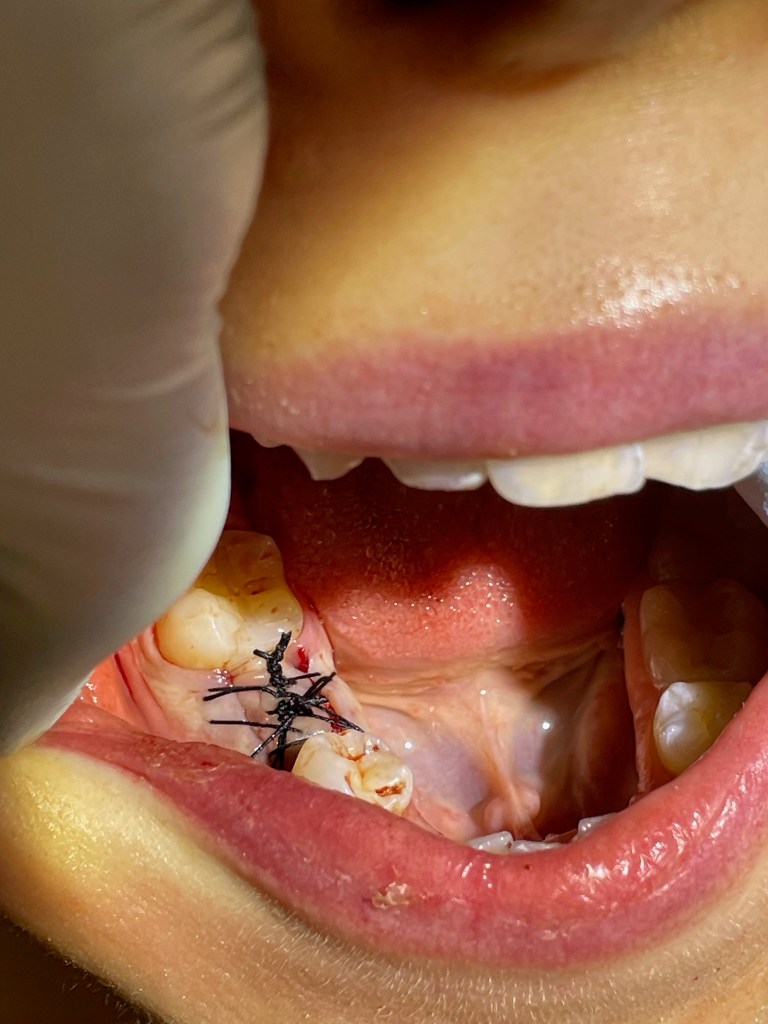

So I took a plug. This was an Osteogen plug from Impladent. In a matter of a few minutes, I

removed the plug from the packaging, packed it into the socket, and aggressively stitched it up.

This was socket preservation, but nothing like anything I had done before. No particulate, no membrane, no needles in the arm. Definitely no hip harvesting. It was, in essence, an earplug.

A bloody earplug that needed stitches, but still an earplug.